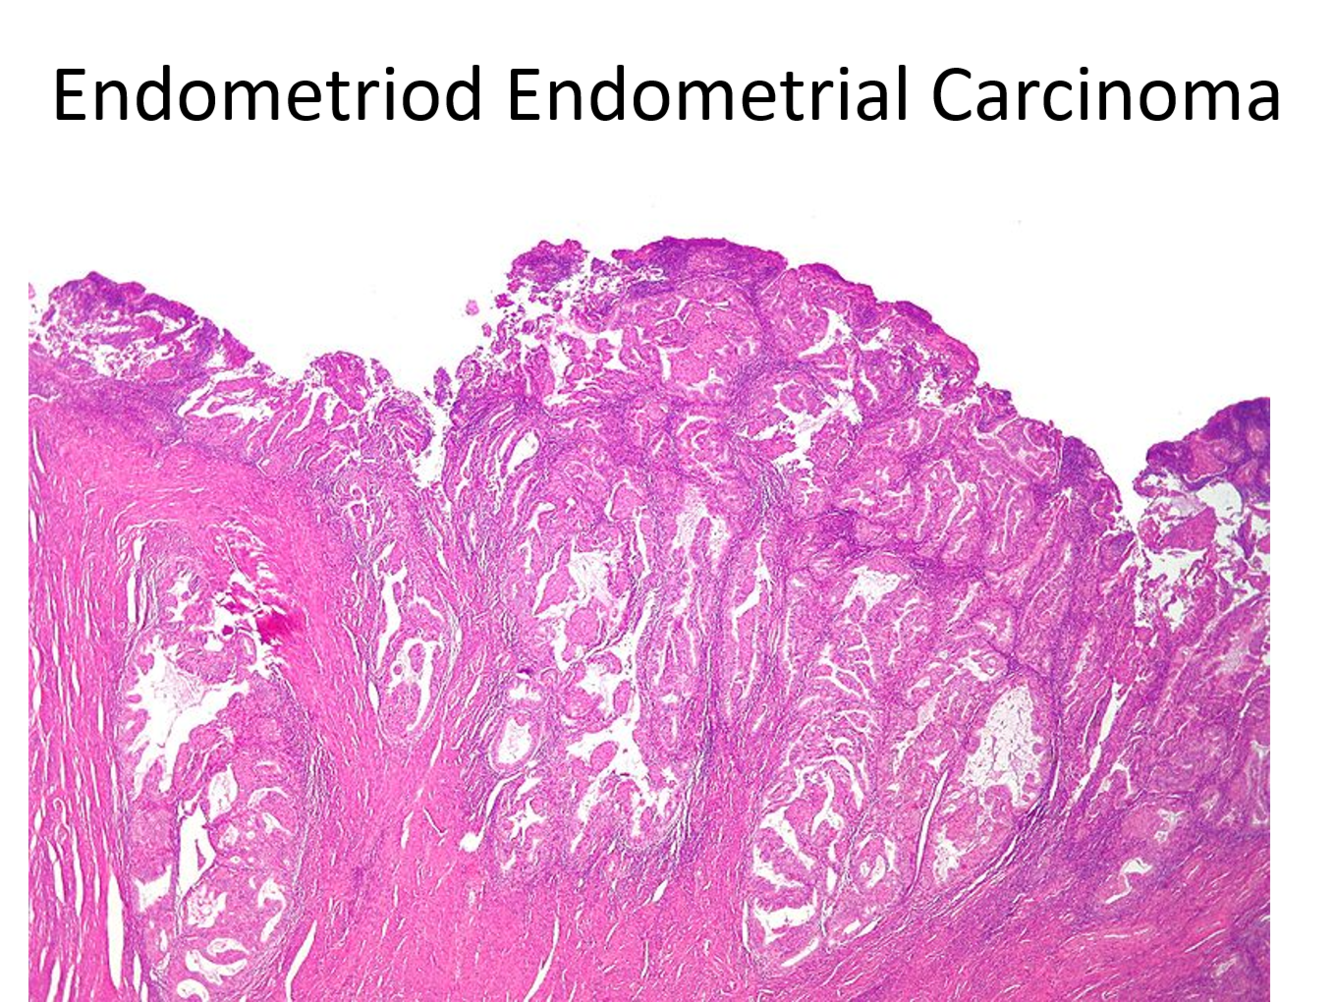

Endometrioid carcinoma are primarily graded by their architecture